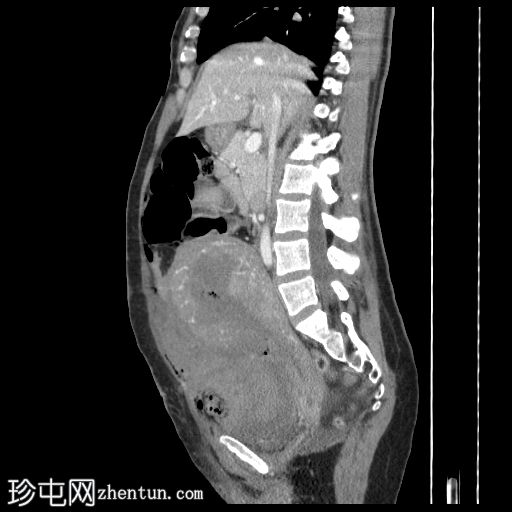

矢状位增强扫描

门静脉期

子宫增大,复旧不全,子宫体前壁全层缺损,位于近期剖宫产部位,气体和液体从子宫内膜腔经壁缺损扩散至子宫外旁组织。

膀胱瓣膜血肿和腹壁血肿较大。

腹腔内有大量游离液体和血腹,无活动性出血。

剖宫产术后子宫破裂是一种罕见但严重的并发症。 CT扫描显示子宫前壁全层存在不规则的低密度缺损,而子宫前壁其他部分则呈规则强化。

气体或液体通过子宫壁缺损从子宫内膜腔扩散至腹膜腔或宫旁腔,可提高诊断的特异性。

辅助征象包括腹腔积血、盆腔血肿和腹腔内游离液体。